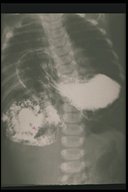

Contrast study outlined the stomach which is herniated into the chest cavity (soft tissue mass shadow ) in a child with hiatal hernia